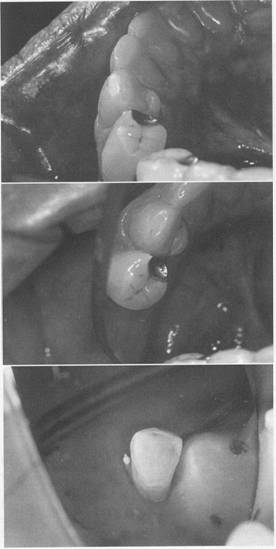

Fig. 6-7 A, Existing cast crown on molar, having previous, minimally prepared rest seats. Rest seats could be recontoured on mesial proximal surface and slight reduction of distal marginal ridge, without fear of penetrating the crown. Mesial and distal occlusal rests (each on an unfavorable inclined plane) were used to direct forces as near axially as possible. B, Lingual view of A. C, Anterior tilt of molar precludes preparation of acceptable rest seat on mesio-occlusal surface. Patient could not afford crown to improve axial alignment or orthodontic treatment to upright the molar. Occlusal rests (arrows) were used on mesio-occlusal and disto-occlusal surfaces to support restoration and direct forces over greatest root mass of abutment.

c